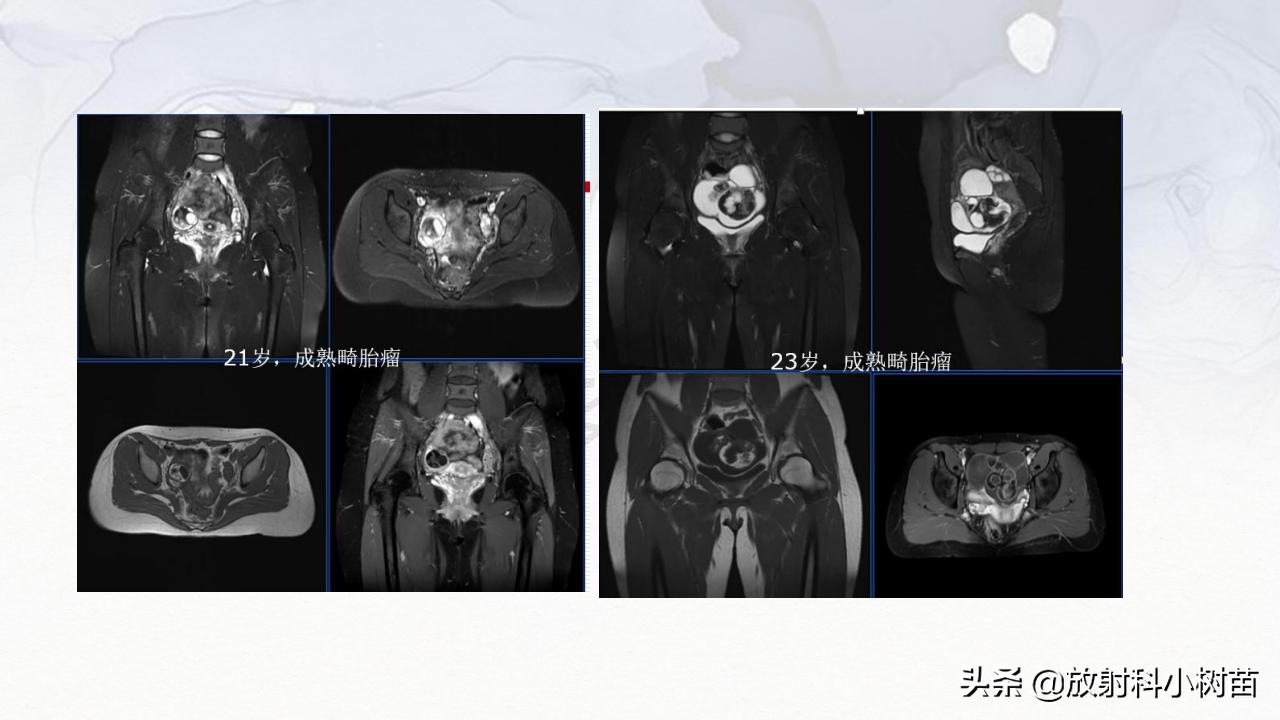

成熟、非成熟畸胎瘤 无性细胞瘤 内胚窦瘤(又称卵黄囊瘤) 绒毛膜癌 胚胎癌